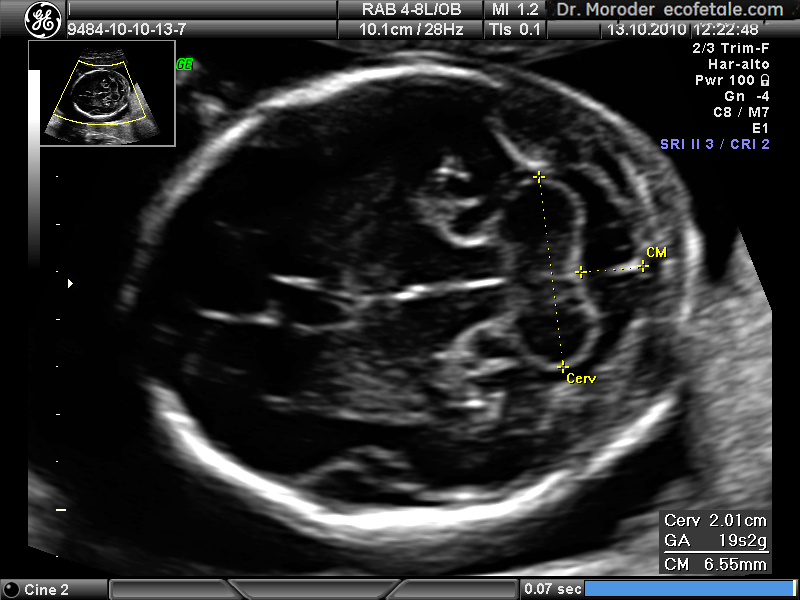

선천성 기형, 유전성 질환, 후천성 질환은 소뇌 구조와 기능에 영향을 미친다. 비가역적인 경우, 유일한 치료법은 적응을 돕는 것이다.[63] 임신 18~20주차 초음파 검사는 태아 신경관 결손 선별 검사에 사용된다.[64]